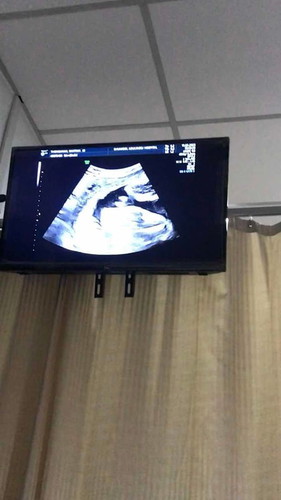

29 สัปดา 5 วัน

ได้ลูกสาวสมใจจิงๆค้ะซาว์ดมาวันนี้เรยอ้าขาโชว์หมอไปทีแต่ขอดูหน้าไม่ให้ดูค้ะเอามือปิดแล้วดีใจกว่าแม่ก็พ่อๆนี่และค้ะ.😊น้ำหนักน้องตอนนี้ 1416 กรัมค้ะ